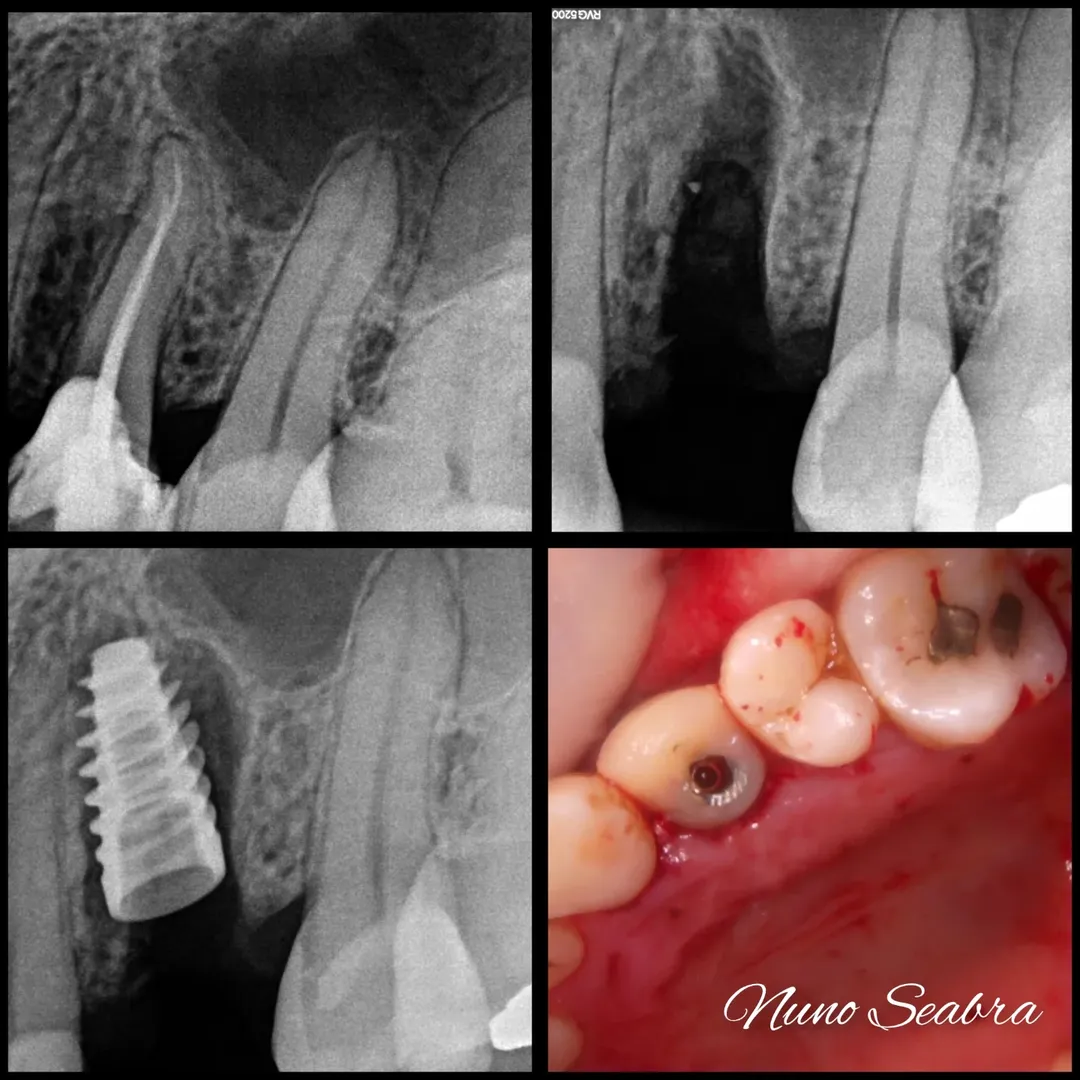

O paciente apresentava um dente comprometido que necessitava de extração. Nas radiografias periapicais, era visível o comprometimento da estrutura dentária, mas as tábuas ósseas circundantes encontravam-se preservadas, o que abria a porta para uma abordagem imediata.

Nas imagens, é possível acompanhar a sequência completa: desde as radiografias iniciais com o dente comprometido, passando pela fase cirúrgica com a extração e colocação do implante, até ao provisório aparafusado em posição. A radiografia final confirma o bom posicionamento do implante e o preenchimento adequado do gap vestibular.